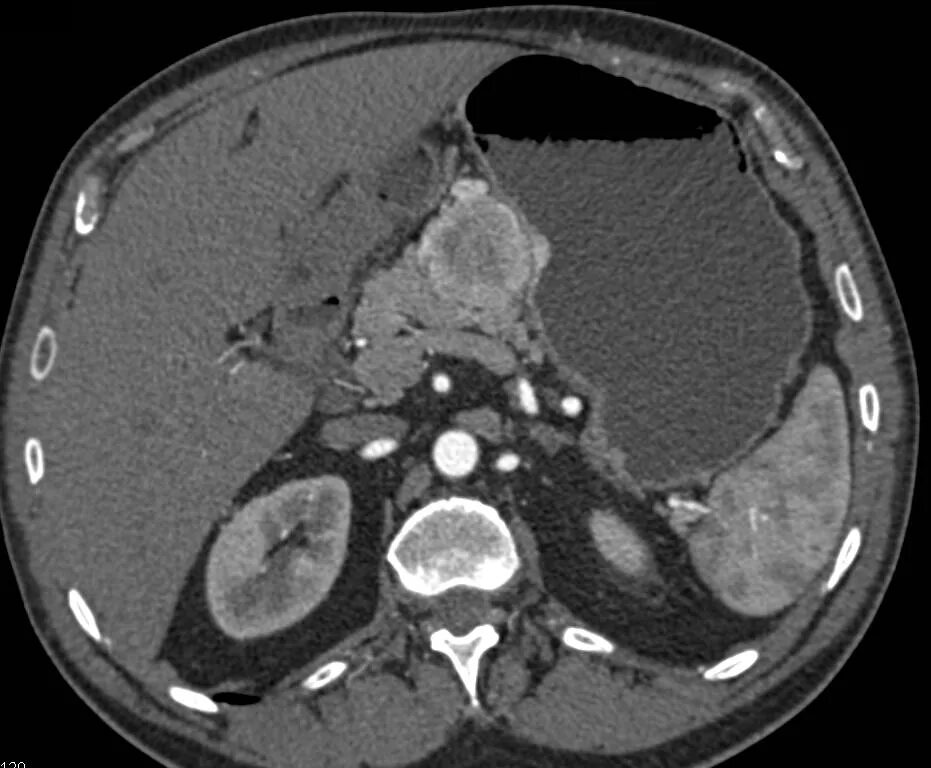

Забрюшинная онкология